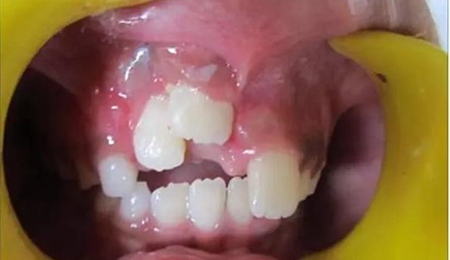

健康的 7 歲男童,前一天摔倒,上頜右中切牙和右側切牙發(fā)生挫入脫位(圖 1)。無牙外傷史,無神經并發(fā)癥病史。檢查發(fā)現(xiàn)雙側下頜下腺增大。

口腔內發(fā)現(xiàn):混合牙列早期,覆蓋正常,安氏I類磨牙關系。牙11和12齦緣紅腫。

牙11,12 和21對叩診敏感。牙11嚴重挫入(牙11和牙12的切緣相差7毫米),并挫入牙槽窩。與牙21相比,牙12大約挫入4毫米。

診斷:牙11嚴重挫入,牙12中度挫入,牙21震蕩傷。